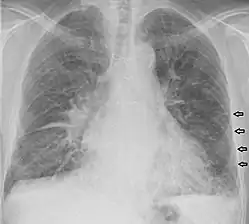

Kerley B lines

These are short parallel lines at the lung periphery. These lines represent interlobular septa, which are usually less than 1 cm in length and parallel to one another at right angles to the pleura. They are located peripherally in contact with the pleura, but are generally absent along fissural surfaces. They may be seen in any zone but are most frequently observed at the lung bases at the costophrenic angles on the PA radiograph, and in the substernal region on lateral radiographs.[3] Causes of Kerley B lines include pulmonary edema, lymphangitis carcinomatosa and malignant lymphoma, viral and mycoplasmal pneumonia, interstitial pulmonary fibrosis, pneumoconiosis, and sarcoidosis. They can be an evanescent sign on the chest x-ray of a patient in and out of heart failure.